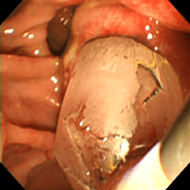

小腸内視鏡によるクリッピング止血処置

小腸内視鏡検査

当院では主にカプセル内視鏡で発見された出血源や腫瘍に対しての止血処置・精査として行っております。小腸内視鏡を常備している施設は決して多いとは言えず、近隣施設からも小腸の精査目的に多数のご紹介を頂いております。